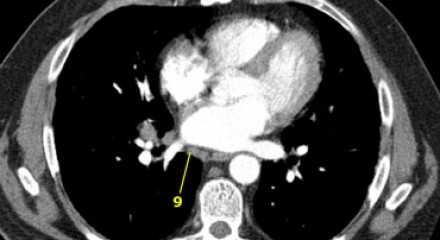

9. лимфатические узлы легочной связки

Данные лимфатические узлы лежат в пределах легочной связки, в том числе и по ходу нижней легочной вены. Легочная связка представлена дупликатурой медиастинальной плевры охватывающей корень легкого.

![15]()